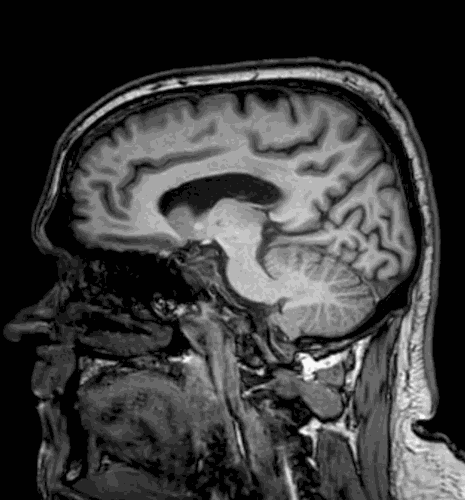

Jaime's brain scan. (SWNS)